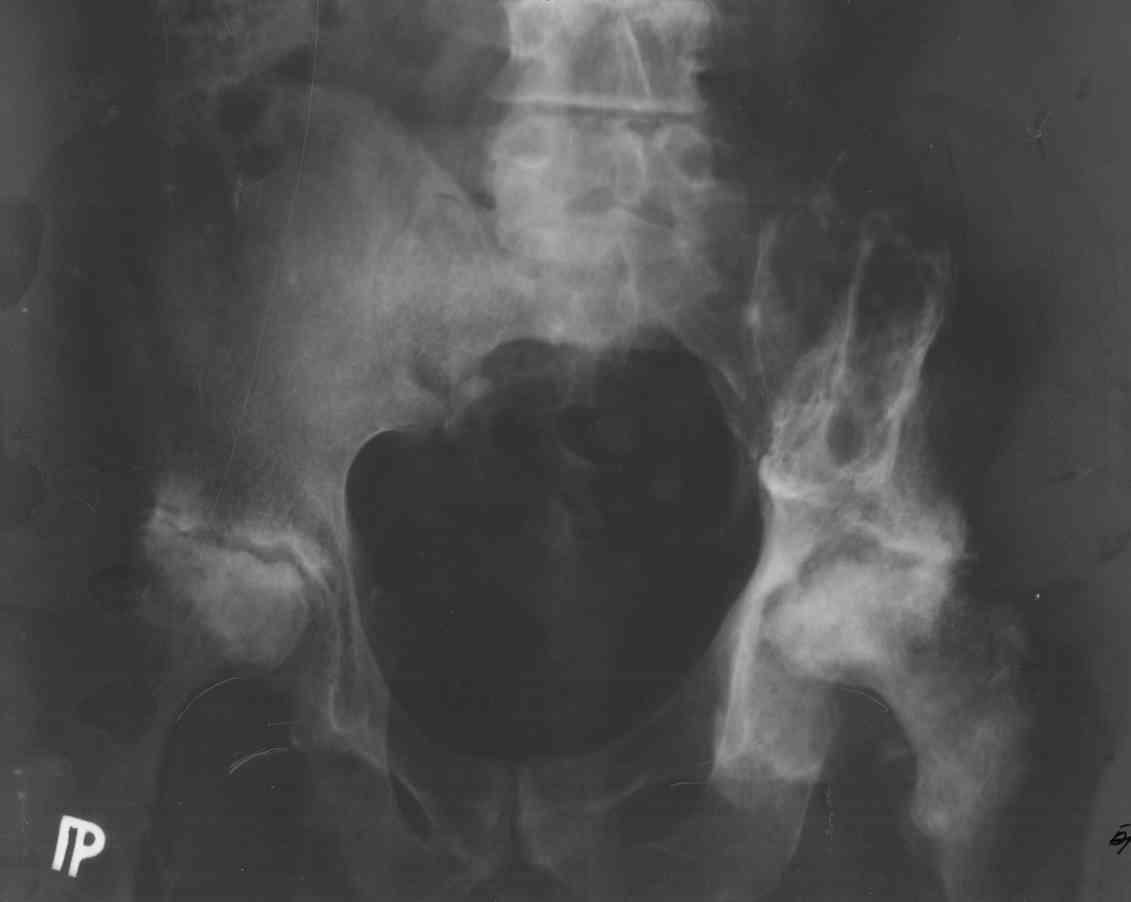

Возможно это очаги болезни. Прилагаю снимок.

Привет Андрей. Похоже, что это у Вашего пациента миеломная болезнь с множественными локусами, в том числе и в тазовых костях и в проксимальных

бедрах. Основное лечение у соответствующих специалистов. Возможность возврата локомоции в суставах методом тотальной артропластики возможна

ортопедами в плане симптоматической помощи, при перспективах жизни соответствующего числа лет и высоком риске любых осложнений. Не говоря уж о

высокой стоимости. С уважением А Рыков Хабаровск.